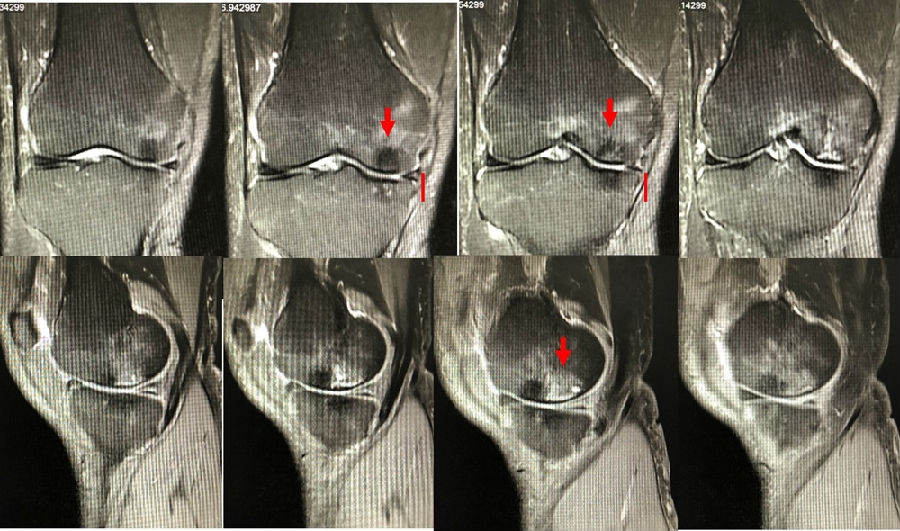

病例1:女,65岁,主诉右膝关节内侧疼痛1周。2018年1月X光未见右膝骨质异常,MR检查见股骨内侧髁骨坏死,半月板相对突出百分比(RPE)28.99%,关节线会聚角1.4°。

予切开行克氏针钻孔减压,口服消炎止痛药物、钙剂及骨化三醇,不负重6周,后改部分负重至3个月。2018年4月复查MR见骨髓水肿基本完全吸收,坏死区局限并修复良好,半月板相对突出百分比(RPE)32.08%,患者临床症状消失。

病例2:女,69岁,主诉左膝关节内侧疼痛1月余。2017年11月X光见右膝股骨髁负重区的软骨下区域出现了椭圆形透亮影,MR检查见股骨内侧髁骨坏死,合并内侧半月板外突和后角层裂,半月板相对突出百分比(RPE)25.32%,矢状位病变区域前后径为23.96mm,关节线会聚角6°。

予克氏针钻减压,消炎止痛药物口服、静滴唑来膦酸钠注射液,避免负重6周,后改部分负重至3个月,患者依从性差。2018年1月复查MR见骨髓水肿少许吸收,坏死区扩大,半月板相对突出百分比(RPE)33.53%,矢状位病变区域前后径为26.89mm,患者仍有膝关节疼痛症状,建议行手术治疗,患者拒绝手术后失访。